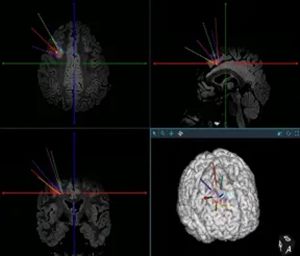

经过详细的术前评估,神经外科二病区李培栋主任和李信晓博士团队设定了精密的手术方案,精准植入了6根颅内电极,刚好将病灶完整包围。

640 (2)_副本

这,就是立体定向脑电图(SEEG)技术。

640 (3)_副本

在接下来的几天里,通过电极直接记录到了发作期异常放电的源头,进一步验证了它就是真正的“元凶”。更关键的是,电极的覆盖范围足够精密,明确了病灶边界,且避开了重要的功能区——这意味着,我们不仅能抓住它,还能就地解决它。